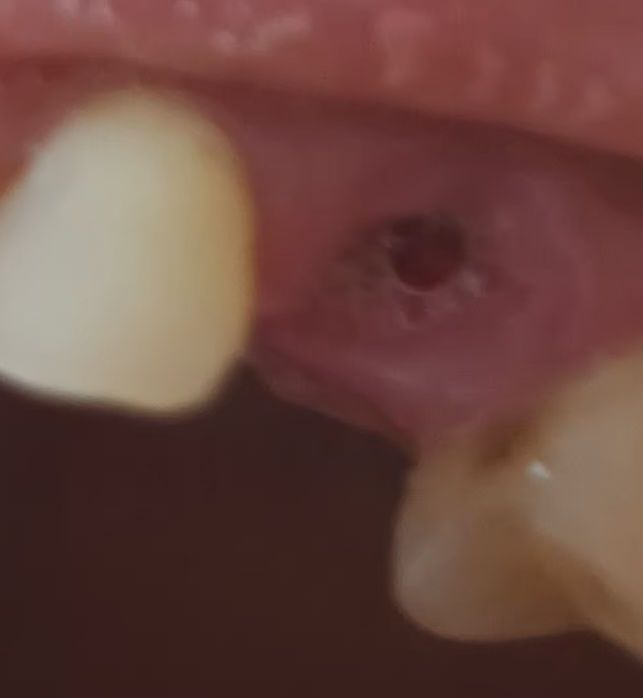

사진은송곳니고 3일차 약을먹어도 욱신정도 좀 통증있고 열과두통 왼쪽아랫니치아앞치아 광대가 좀아픕니다 오늘은 입이건조하고 냄새가 살짝납니다

드라이소켓일까요 ? 부비동염으로 항생제 한달먹고 누런악취콧물 안면통증은 줄어들었으나

치통이지속돼 치과가니 뽑자고해서 윗어금니

세개뿌리남은걸 뽑았습니다

부비동염이있는데 뽑아서 더 아픈가싶고요ㅠ 드라이소켓인가 싶어 걱정됩니다ㅠ

사진상으로는 드라이소켓의 양상이 보이진 않습니다. 통증이나 악취의 정도가 심하다면 치과 가보시는 게 좋습니다.

사진상드라이소켓은 아닌 것으로 보이며, 발치후 1-2주간은 통증이 발생할수 있습니다. 발치부위에 음식물 찌꺼기가 남지 않도록 꼼꼼히 양치하여 관리하여 주길 권하며, 헥사메딘 소독용 가글액으로 관리하는 것을 권합니다.

사진으로는 크게 문제가 있는것으로 보이지는 않습니다.